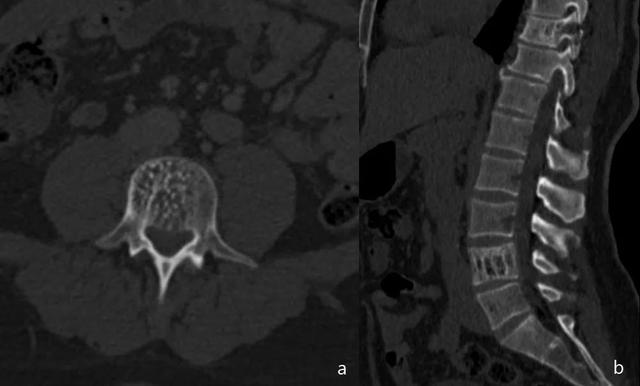

在脊柱中,它们呈现为射线可透过的病变,在椎体中具有厚的小梁垂直图案,其可以延伸到椎弓根和椎板。鉴别诊断包括骨质疏松症和佩吉特病。

脊柱外病变以射线可透性病变表现,轻度扩张,轮廓分明,有小梁状。可见皮质变薄和骨扩张(图17)。

图17:椎骨血管瘤。轴向CT(a)显示由于椎骨小梁增增粗,成砂砾样改变。矢状面成像(b)可见栅栏样改变,指的是垂直取向的,增厚的小梁。